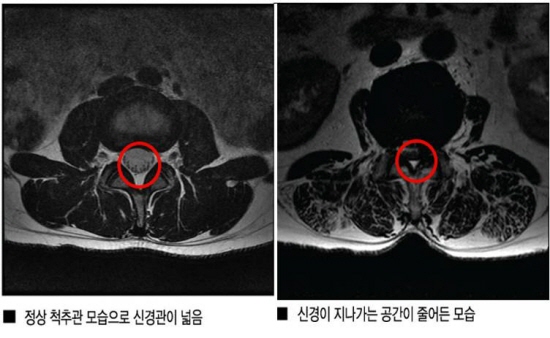

척추관협착증, 안정성 높은 ‘이완추나’가 해법

척추관협착증, 비수술 한방 ABCDE 치료효과 '굿'